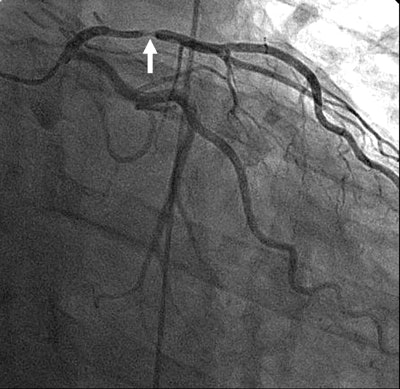

| Images 1-7 shown top to bottom: A 59-year-old man presented with atypical chest pain. A circumscribed, short-segment high-degree stenosis (arrow) in the proximal LAD is difficult to detect on transverse (1), sagittal (2), or coronal (3) multiplanar reformats. Use of advanced visualization tools with automated extraction of the coronary artery tree (4) and automated display as curved multiplanar reformat (5) clearly identifies the lesion, also seen in the 3D view (6) and confirmed on conventional catheter angiography (7). All images courtesy of Dr. U. Joseph Schoepf. |